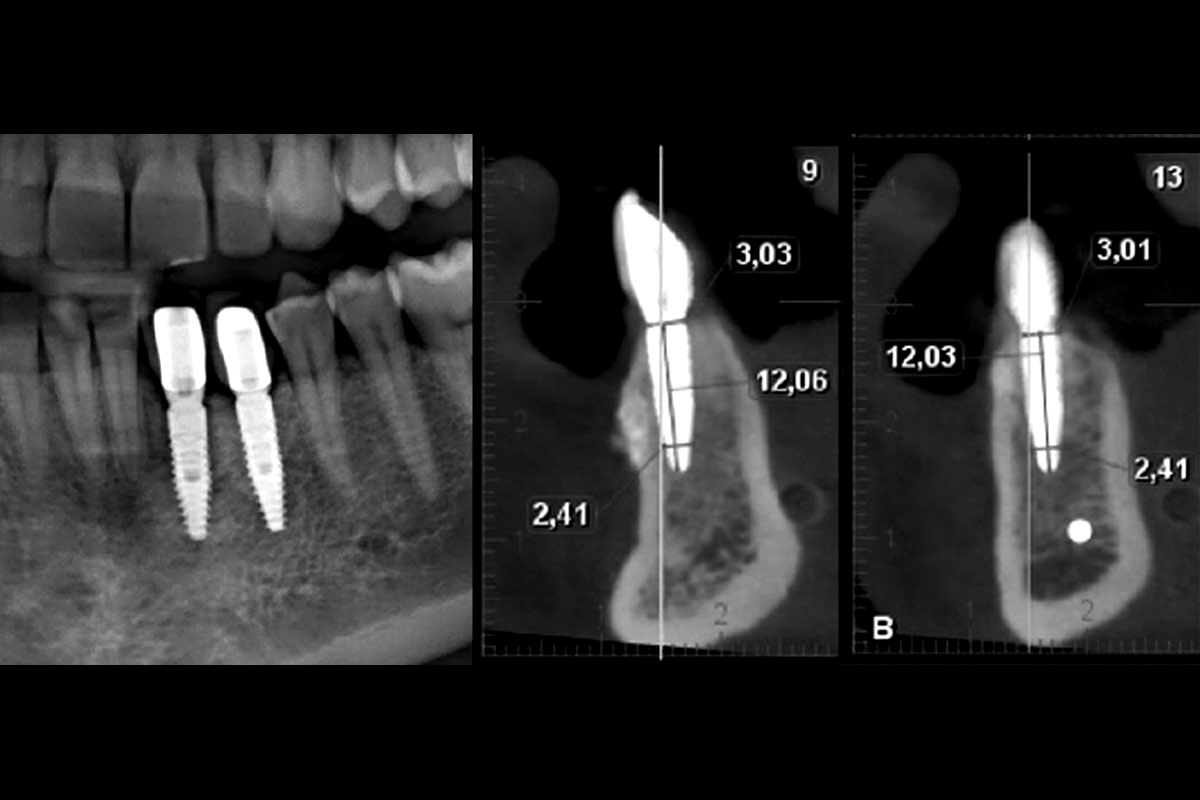

12/15 - Panoramic x-ray after prosthesis confirms bone stability around implantsTreatment of vertical bone loss by using cerabone®, autologous bone and Jason® membrane - Prof. Rafael Ortega Lopes

13/15 - CBCT after 3 years indicates sufficient bone thickness to obtain long-term stable resultsTreatment of vertical bone loss by using cerabone®, autologous bone and Jason® membrane - Prof. Rafael Ortega Lopes